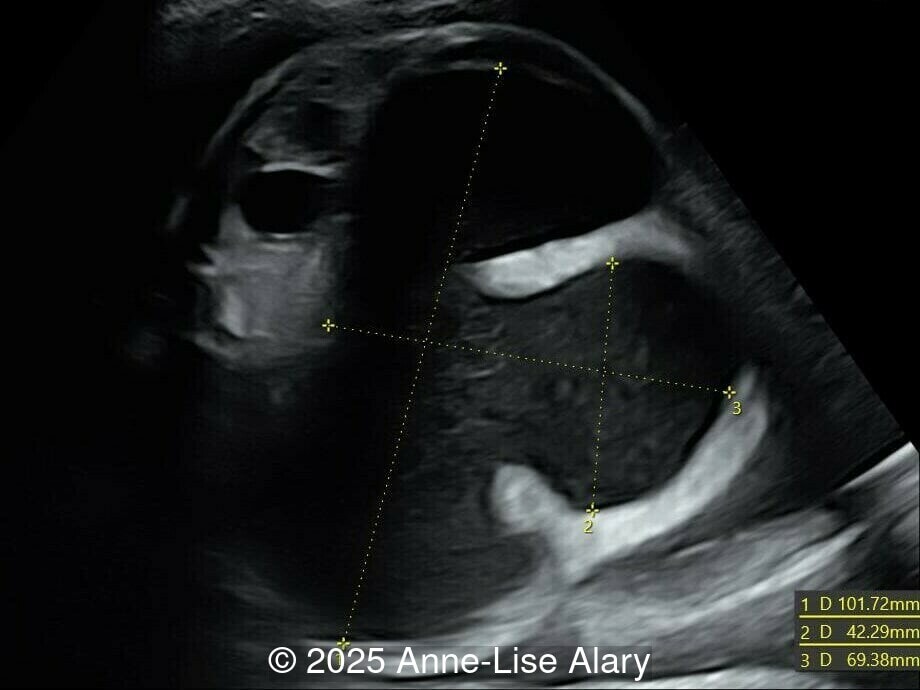

Axial image of the abdomen

Image 1 Axial image of the abdomen

Our prenatal ultrasound revealed a male fetus with megabladder, dilation of both ureter and kidneys, and thinned kidney parenchyma consistent with Lower Urinary Tract Obstruction (LUTO).  Additional findings suspected on ultrasound and confirmed on computed tomography included:

The diagnosis of PBS is often made in the second trimester of pregnancy, although it has been described as early as 11 weeks of gestation [20]. The most frequent ultrasound findings are a large, thin-walled bladder accompanied by bilateral hydroureter/hydronephrosis, dysplastic kidneys with echogenic renal parenchyma and renal cortical cysts, and abdominal wall laxity which is better viewed after bladder decompression [21]. Cryptorchidism can be detected prenatally by 28 to 30 weeks gestation when the testes descend into scrotum. There may be a patent urachus, visible as a cystic connection between bladder and umbilicus. Oligohydramnios is a frequent finding, which makes it difficult to visualize the associated anomalies.